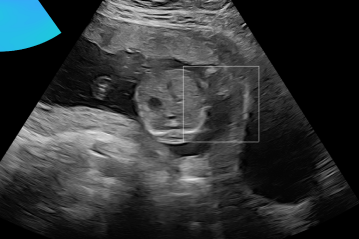

Three in vivo Bmode fetal images with and without aberration correction are presented in Figs. 10-12. GIF images of examples A-L (see Fig. 9 and Table 5) alternating between the corrected and uncorrected images are uploaded as supplementary material. The differences in image quality are easier to appreciate in the GIFs than in a side-by-side comparison. The data points for the three examples are colored black in Fig. 9. Table 5 give tabular values for the global sound speed estimate, sharpness increase (κ𝜅\kappa) and answers from the clinical evaluations.

Refer to caption

(a) Uncorrected Bmode.

(b) Aberration corrected Bmode.

(c) Uncorrected Bmode.

(d) Corrected Bmode.

Figure 12: Example C. In vivo fetal Bmode and coherence images using constant 1540 m/stimes1540dividemetersecond1540\text{\,}\mathrm{m}\text{/}\mathrm{s} and the estimated average sound speed map. The average sound speed map is shown in the top right corner and the rightmost colorbar indicates the sound speed values. Alternating GIFs are found in the supplementary material.

The in vivo examples A-C, in Figs. 10-12 respectively, show different nuances of how sound speed aberration correction improves focusing quality. A noticeable improvement in Fig. 10 is the improved contrast and clarity of borders. The sound speed correction seems to remove the double structure indicated by the arrows in Figs. 10c-10d. The skull border and the brain structures in Fig. 11 are also better defined and clearer after aberration correction. Example C in Fig. 12 is the image with the highest increase in Tenengrad κ𝜅\kappa, seen from Fig. 9 and Table 5. The improvement in image quality is evident around the boundary of the fetus body and the correction sharpens the structures indicated by the arrows. The improved contrast between the layers in the shallow tissue layers is also noticeable.